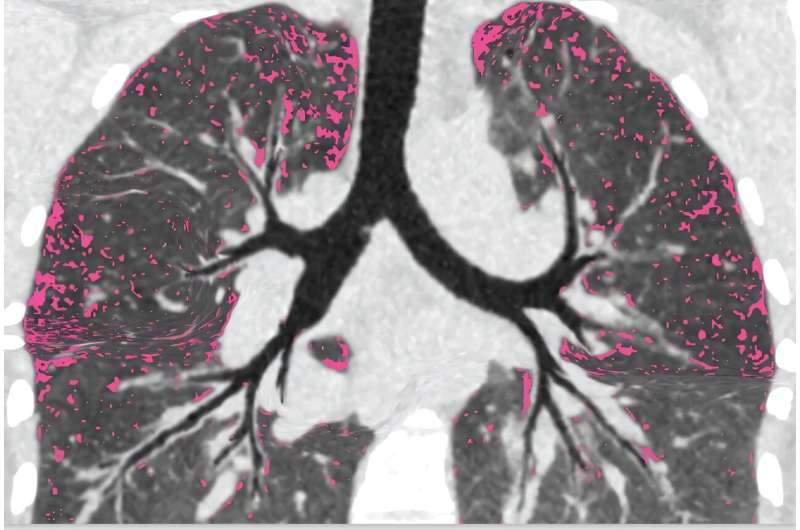

Avant que les participants à l’étude ne commencent sur des modulateurs, les chercheurs sont entrés dans les poumons des patients avec des caméras minces appelées bronchoscopes. Ils ont échantillonné des régions qui différaient par la quantité de dommages, d’infection et d’inflammation.

Ils ont ensuite revu les mêmes zones pulmonaires un an après le traitement pour voir où l’infection restait et quelles caractéristiques pulmonaires étaient liées à une infection persistante.

« Une idée principale sur le terrain est que les patients restent infectés parce que les régions pulmonaires très endommagées ne peuvent pas effacer l’infection, similaire à la façon dont les tissus endommagés des plaies sont infectés », a déclaré le pulmonologue de médecine UW, le Dr Sid Kapnadak, qui a dirigé un échantillonnage pulmonaire pour l’étude. « Si un processus similaire est responsable des infections pulmonaires persistantes CF, la recherche peut se concentrer sur ces domaines. »

Durfey a poursuivi: « Cependant, les personnes qui sont restées infectées avaient une infection et une inflammation partout où nous regardons, y compris les zones pulmonaires avec très peu de dégâts. »

Ces résultats suggèrent que les dommages pourraient ne pas être la principale cause de la persistance des infections et soulever que la fonction pulmonaire chez les personnes infectées bactériennes pourrait continuer de se détériorer.